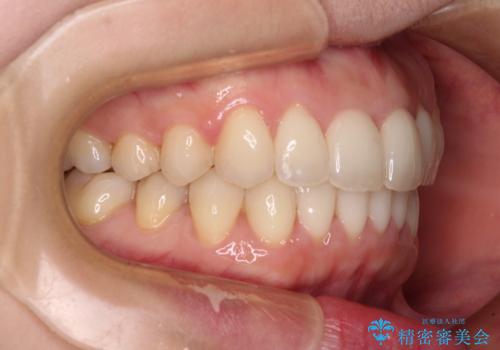

出産をしながら歯列を整える インビザラインによる矯正治療

- 上下の前歯のデコボコを気にして来院された患者様です。

妊娠中であり、途中通院が難しくなる可能性があることから、インビザラインによる矯正治療を行うこととしました。

上下顎歯列全体の後方移動とIPR(歯と歯の間を削る)によってデコボコが解消するように設計しました。